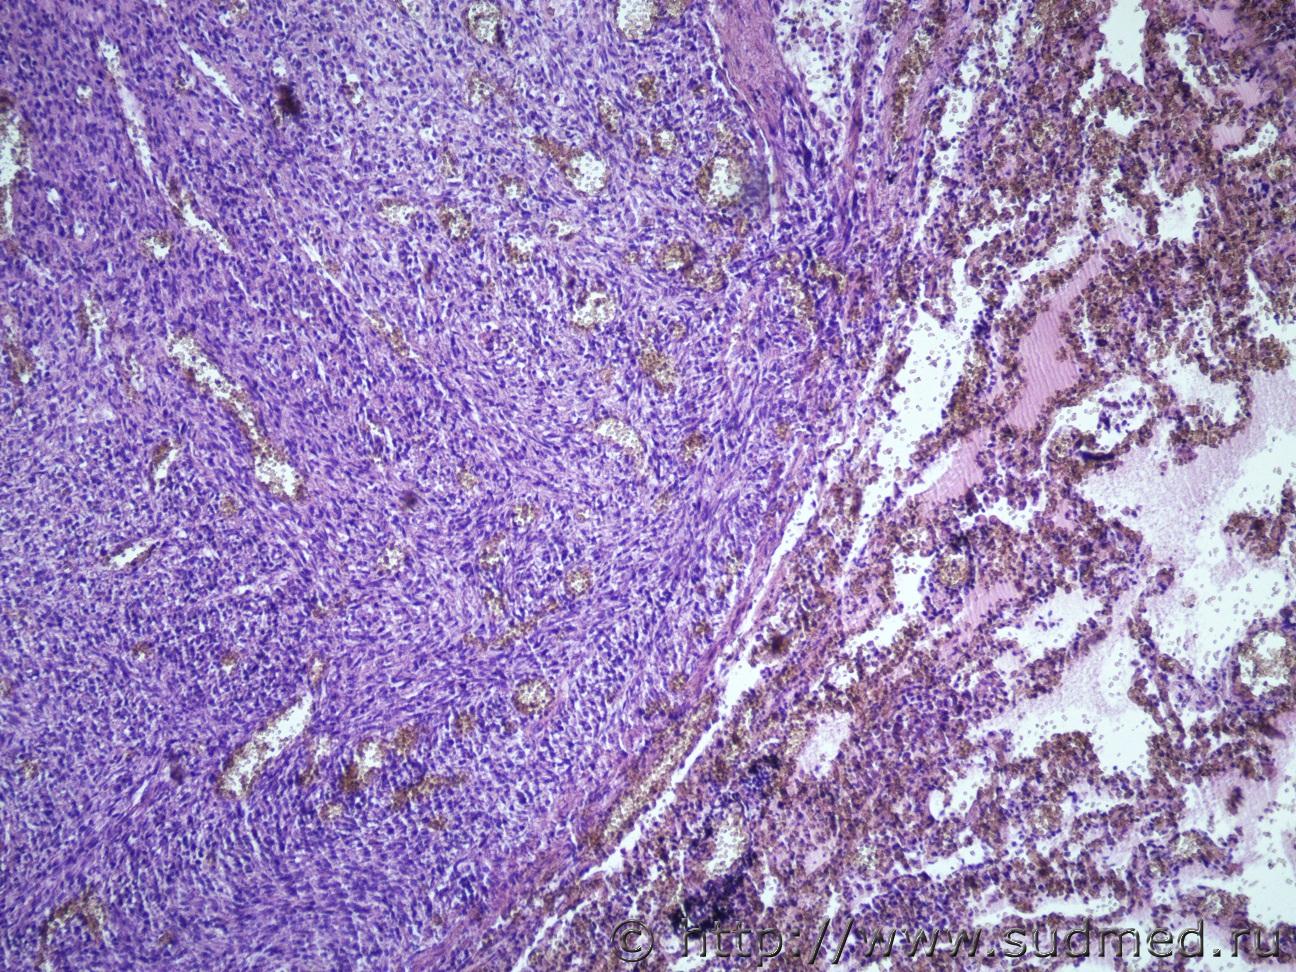

Ув. коллеги нужна помощь))) Муж 80 лет. На вскрытии рак щитовидной железы с метастазами в легкие

легкиеСудебная медицина - Прикрепленное изображение Судебная медицина - Прикрепленное изображениеСудебная медицина - Прикрепленное изображениеСудебная медицина - Прикрепленное изображение 12 лет назад был рак желудка и 12-перс. кишки, оперирован.

Подумала бы о медуллярном раке щитовидной железы.

Похож,но не исключил бы криброзно-морулярный.

По щитовидке похоже на медуллярный тип карциномы, а в легких напоминает солитарную фиброзную опухоль? Но ТС -у виднее.

морфологическая картина соответствует медуллярному раку.